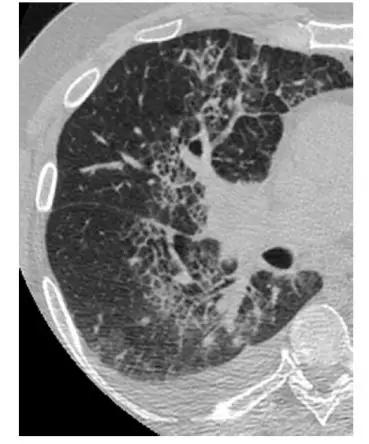

*慢性HP 下叶水平的HRCT表现为粗大的“网状图案”,伴有牵张性支气管扩张和支气管扩张,小叶内和支气管血管间质增厚以及磨玻璃样改变。小叶密度减低为慢性超敏性肺炎的诊断提供了“关键”证据。